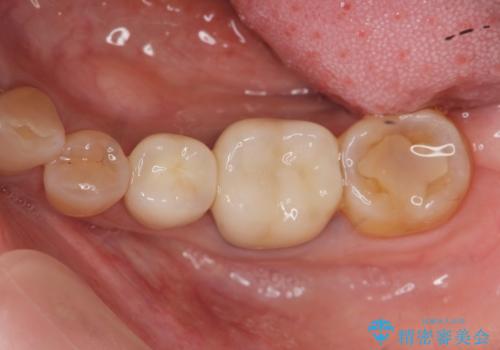

- 「老朽化し古くなった銀歯を白いものにやりかえたい。」と希望され来院されました。

銀歯の下には再発した虫歯やセメントの漏出が見られ、丁寧に除去したのちセラミックによるクラウン・ブリッジ補綴を行います。